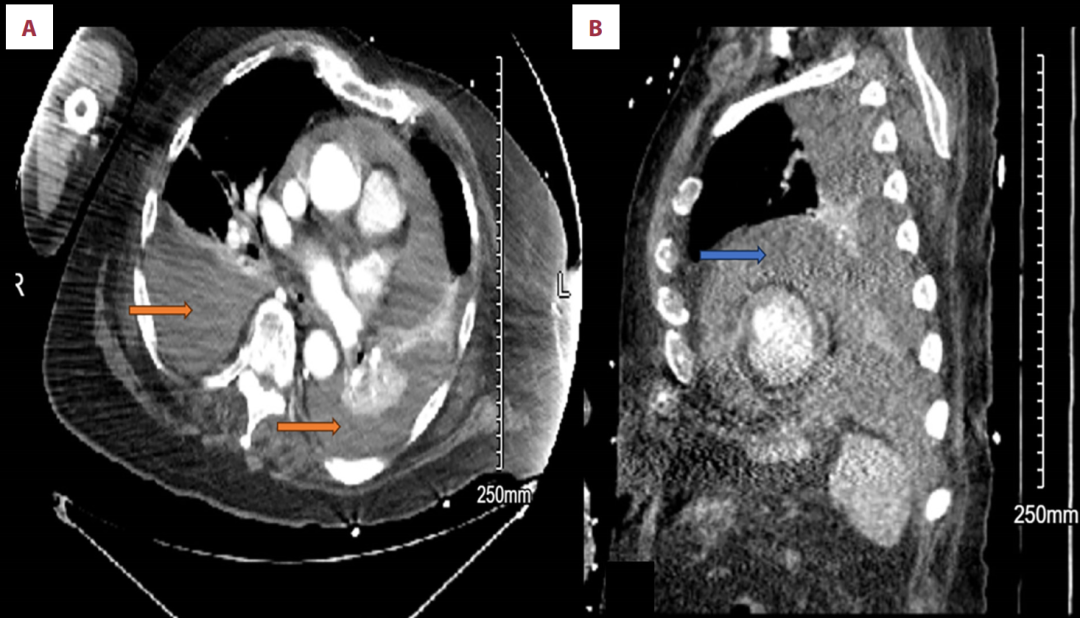

胸部CT发现中度至大量的双侧胸腔积液(左侧多于右侧)和中度至大量心包积液,两者可能为血性。同时发现4.3cm的升主动脉瘤。

Contrast-enhanced axial chest CT shows bilateral pleural effusions (orange arrows) with high attenuation, consistent with hemorrhagic effusions (A). The density (Hounsfield units) is higher than simple fluid, supporting the presence of blood within the pleural spaces. Contrast-enhanced sagittal chest CT demonstrates a large pericardial effusion (blue arrow) with increased attenuation, indicating a hemorrhagic pericardial effusion. This effusion surrounds the heart and is of higher density than simple serous fluid, consistent with blood (B).